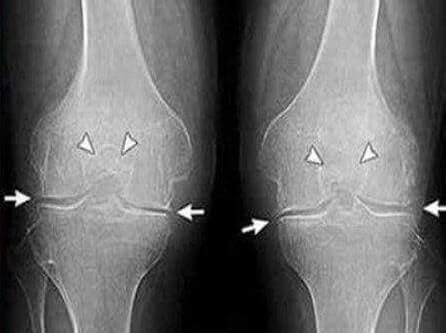

5 месяцев: сдала анализы и сделала рентген. Никаких

следов артроза! Хрящи в суставах как у 20-ти летней

девчонки. Докторша сказала, что на предыдущем рентгене скорее всего

был дефект, поэтому диагноз артроз был ошибочным.